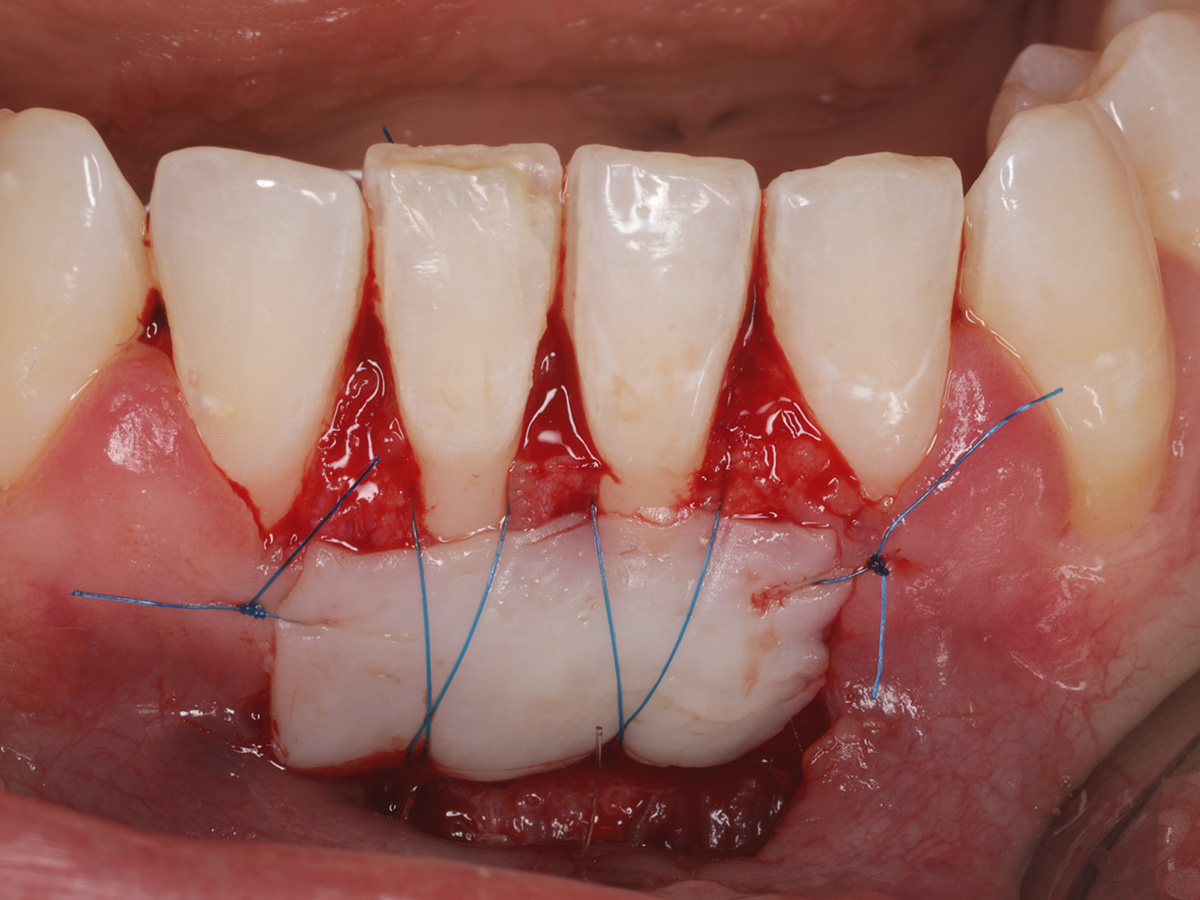

Abbildung 3

Fixation des FST mit Kreuz- und Einzelkopfnähten.